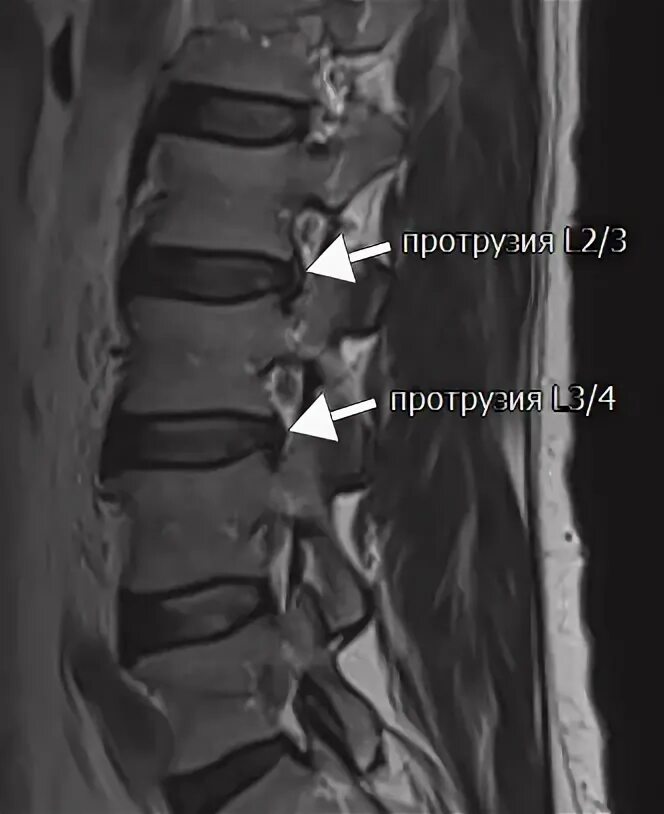

Мрт крестово поясничного отдела